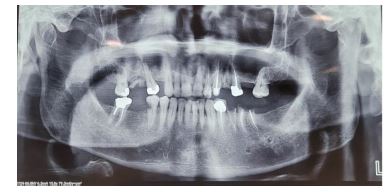

گزارش مورد : بیمار مردی ۵۷ ساله، بدون سابقه بیماری سیستمیک خاص، با شکایت تورم مزمن، بدون درد و با رشد آهسته در ناحیه قدامی ماگزیلا از 1سال گذشته در اسفندماه 1402 به درمانگاه دندانپزشکی مراجعه کرده و پس از بیوپسی و شک به OKC بیمار توسط دندانپزشک به سرویس جراحی دهان و فک و صورت بیمارستان شهید رهنمون یزد ارجاع داده شد. تورم طی یک سال گذشته بهتدریج افزایش یافته بود و با مصرف دارو یا اقدامات دندانی پیشین بهبود نیافته بود. بیمار سابقه ضربه یا جراحی قبلی در این ناحیه نداشت. در معاینه خارجدهانی، تورم غیرقرینه در ناحیه زیر بینی و لب فوقانی مشاهده شد که موجب برهمخوردن خفیف تقارن صورت شده بود. پوست روی ناحیه متورم طبیعی و فاقد تغییر رنگ یا زخم بود (شکل 1و2) (نمای تحتانی صورت نیز برجستگی پایه بینی و ناحیه سابنازال را تأیید کرد. در معاینه داخلدهانی، تورم سفت و بدون درد در مخاط لبی ماگزیلا از ناحیه مولر دوم سمت راست تا مولر دوم سمت چپ دیده شد. مخاط روی ضایعه اندکی قرمزتر از مخاط مجاور بود، ولی زخم، ترشح یا التهاب حاد مشاهده نشد (شکل 3). رادیوگرافی پانورامیک اولیه، ضایعهای رادیولوسنت، تکحفرهای و با حدود مشخص را در ناحیه قدام وخلف ماگزیلا نشان داد که از دندان مولردوم سمت راست تا مولر دوم سمت چپ امتداد داشت و منجر به نازکشدگی قابلتوجه کورتکس قدامی شده بود (شکل ۴). ارزیابی تکمیلی باCBCT، ضایعهای با گسترش وسیع (2*3*4 سانتیمتر) در محور قدامی-خلفی فک بالا را تأیید کرد که بدون درگیری سینوس فکی یا کف بینی بود. دیوارههای استخوانی پالاتال و باکال در محل ضایعه نازک شده اما پیوسته بودند. جابهجایی اندک ریشههای دندانهای مجاور بدون تحلیل ریشه مشاهده شد (شکل 5). با توجه به ویژگیهای بالینی و تصویربرداری، تشخیصهای افتراقی شامل آملوبلاستوما، کیست مجرای نازوپالاتین و OKC مطرح شد. بیوپسی انسیزیونی از ضایعه انجام و نمونه جهت بررسی هیستوپاتولوژیک ارسال شد. گزارش پاتولوژی نشان داد که ضایعه دارای اپیتلیوم سنگفرشی مطبق پاراکراتینیزه با سطح مواج و چینخورده، بدون رتپگ، و لایه بازال نردبانی با سلولهای استوانهای پلاریزه است. کراتین فراوان در لومن مشاهده شد و میتوز در لایههای بازال و پارابازال وجود داشت. این ویژگیها با تشخیص OKC نوع پاراکراتینیزه مطابقت داشتند (شکل 7). با توجه به محل ضایعه، اندازه نسبتاً بزرگ آن، و نزدیکی به ساختارهای حیاتی مانند حفره بینی و قاعده سینوس، تصمیم به انجام درمان مرحلهای گرفته شد. در مرحله اول، مارسوپیالیزاسیون تحت بیهوشی عمومی با اینتوباسیون نازال انجام شد. برش وستیبولار دوطرفه در قدام ماگزیلا ایجاد و پس از بازکردن دیواره کیست، دو عدد درن نلاتون در طرفین ضایعه قرار داده شد. بخیه لبههای مخاطی به دیواره کیست با نخ سلیک ۰-۲ انجام و مخاط با ویکریل ۰-۳ سوچور شد. شستشوی کامل با نرمالسالین انجام شد و پانسمان داخل حفره با گاز استریل صورت گرفت (شکل 8). تا زمان حضور بیمار در بیمارستان شستشو توسط پزشک انجام شد و نهایتا پس از آموزش شستشو به بیمار و اطمینان از آموزش وی بیمار مرخص گردید. در پیگیریهای انجام شده در فواصل دو هفته، یک ماه، سه ماه و شش ماه، بیمار بدون علائم عود، درد یا ترشح باقی ماند. تورم بهتدریج کاهش یافت و نمای مخاطی ناحیه به وضعیت نرمال نزدیک شد. گرافی پانورامیک پیگیری شش ماهه کاهش چشمگیر اندازه ضایعه و افزایش تراکم استخوان را نشان داد (شکل 9). با توجه به پاسخ مناسب ضایعه به مرحله اول درمان، برنامهریزی برای انجام انوکلیشن تأخیری به همراه برداشت محیطی (Peripheral Ostectomy) پس از شش ماه انجام شد. در مرحله دوم تحت بیهوشی عمومی، با ایجاد یک برش وستیبولار و نمایان شدن ناحیه ضایعه، پوشش ضایعه از دیوارههای استخوانی جدا گردید. بهمنظور برداشت استخوان مجاور پوشش کیستیک، از فرز جراحی استفاده شد. پس از انجام انوکلیشن، حفره با ژلفوم پر گردید و برشها با نخ بخیه ۴-۰ پرولن بسته شدند. هدف از این اقدام، حذف کامل اپیتلیوم باقیمانده و کاهش خطر عود ضایعه در بلندمدت خواهد بود.

شکل 4: نمای پانورامیک قبل از انجام مارسوپیالیزاسیون که ضایعه رادیولوسنت تکحفرهای در ناحیه قدامی و خلفی ماگزیلا را نشان میدهد. محدوده ضایعه از مولردوم راست تا ناحیه مولردوم چپ امتداد دارد و نازکشدگی کورتکس قابل مشاهده است.